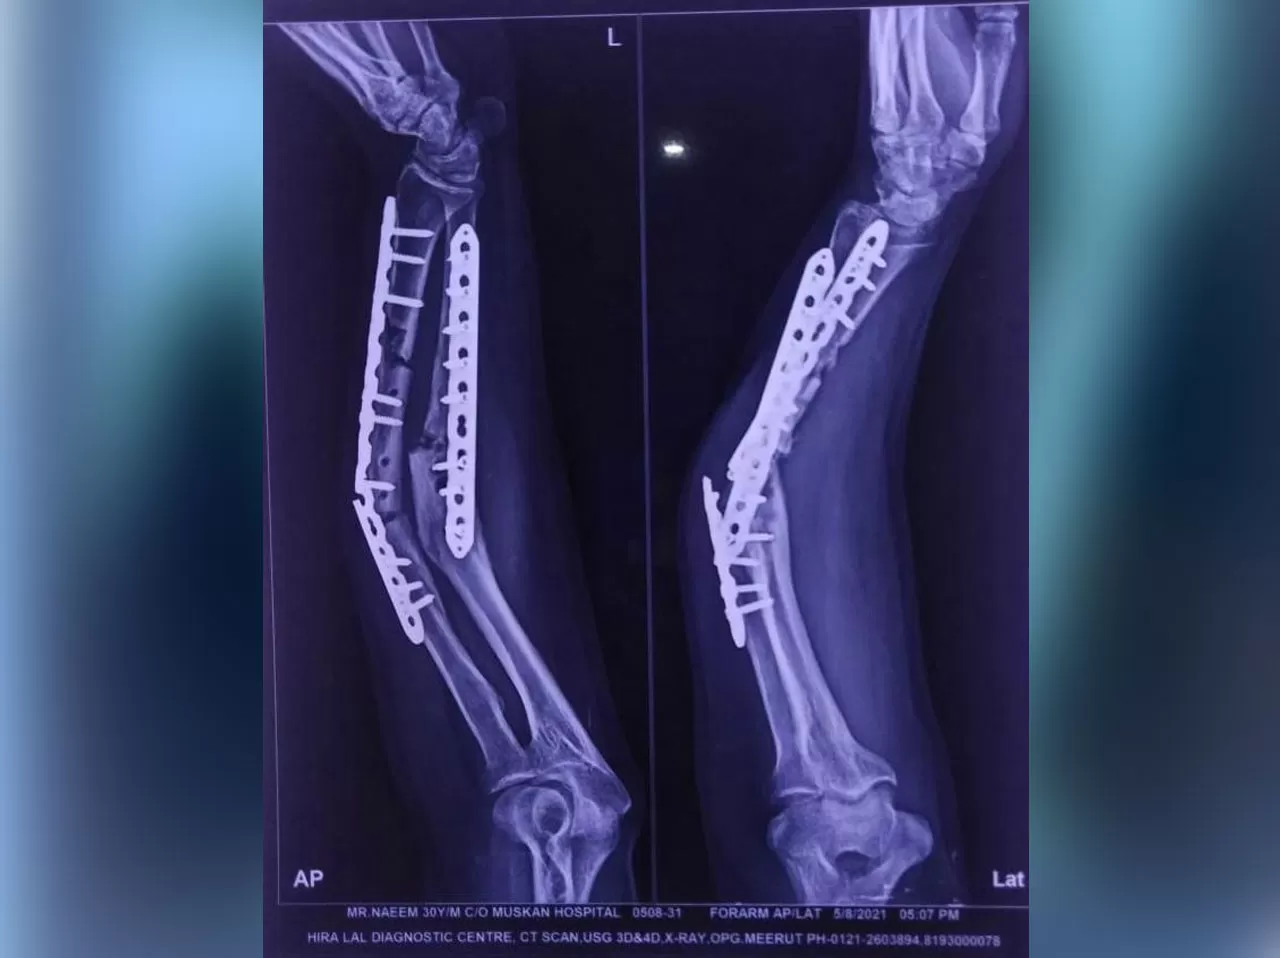

Mr. Naeem

Name: Mr. Naeem

Date of Operation: 5 Aug 2021

Age: 30 Years